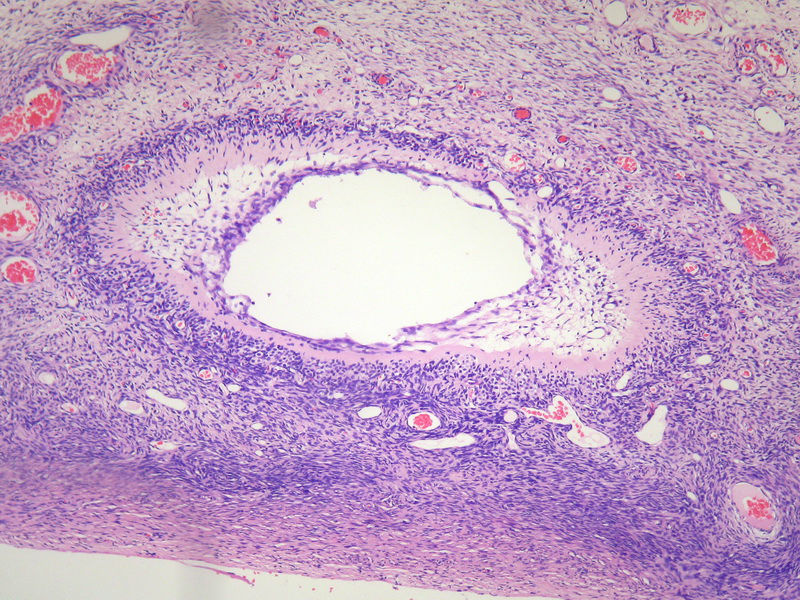

26岁女性,因卵巢肿物行卵巢切除术,照片所示是卵巢什么病变。